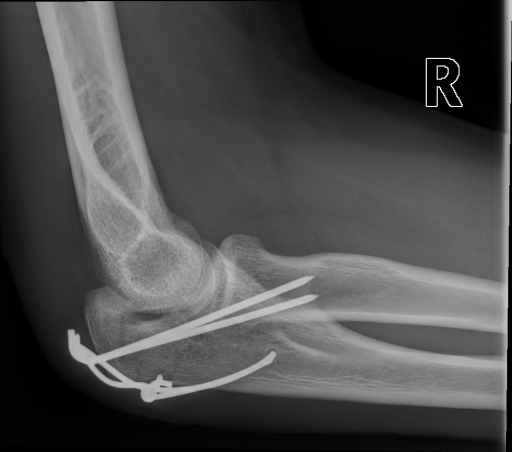

Figure 3 shows some samples images from IRMA dates along with their corresponding IRMA codes.